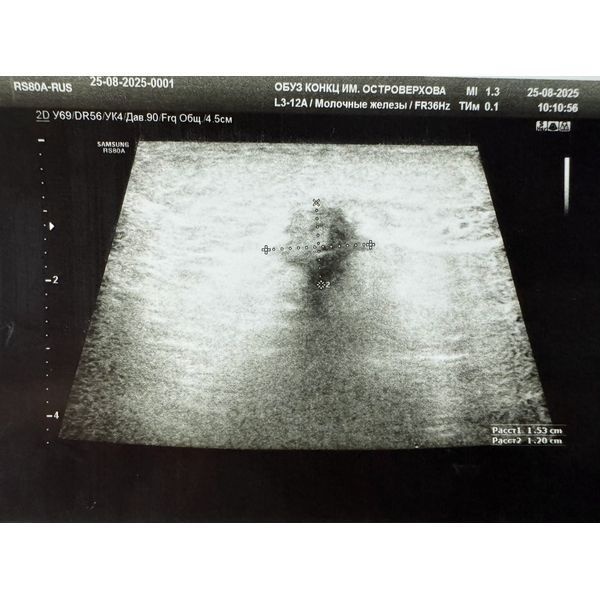

- УЗИ молочных желёз — гипоэхогенное (тёмное) образование с неровными, нечёткими контурами и микрокальцинатами (мелкими известковыми отложениями) в верхненаружном квадранте, также на себя обращал внимание изменённый лимфоузел в подмышечной области;